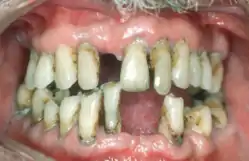

| Periodontal disease | |

| Other names | Gum disease, pyorrhea, periodontitis |

| Symptoms | Red, swollen, painful, bleeding gums, loose teeth, bad breath[1] |

| Complications | Tooth loss, gum abscess[1][2] |

Periodontal disease, also known as gum disease, is a set of inflammatory conditions affecting the tissues surrounding the teeth.[5] In its early stage, called gingivitis, the gums become swollen and red and may bleed.[5] It is considered the main cause of tooth loss for adults worldwide.[7][8] In its more serious form, called periodontitis, the gums can pull away from the tooth, bone can be lost, and the teeth may loosen or fall out.[5] Bad breath may also occur.[1]